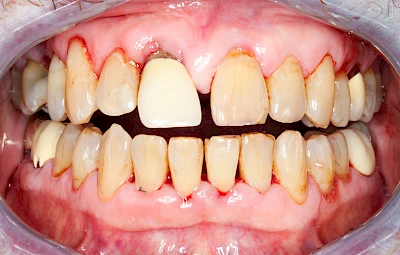

Gingivitis & Parodontitis: Stadien

Ist zunächst nur das Zahnfleisch von der Entzündung betroffen, spricht man von Gingivitis. Später, wenn auch der Knochen um die Zähne herum entzündet ist, spricht man von einer Parodontitis. Bei der Parodontitis wird der Knochen nach und nach abgebaut und das Zahnfleisch zieht sich zurück. Die Zahnhälse und Zahnwurzeloberflächen liegen mehr und mehr frei. Die Zähne werden zunehmend lockerer und fallen schließlich aus.

Bakterien in den Zahnbelägen greifen neben den Zähnen auch das Zahnfleisch (Gingiva) und den gesamten Zahnhalteapparat (Parodont) an. Der Körper reagiert mit einer Entzündung, sichtbar als Rötung und Schwellung. Meist blutet das Zahnfleisch z .B. beim Essen oder auch beim Putzen der Zähne.

Ein schlecht eingestellter Diabetes kann das Entzündungsgeschehen noch verstärken. Raucher haben ein 3-5x höheres Risiko für Parodontitis. Das Zahnfleisch ist schlechter durchblutet, weshalb der Körper die Bakterien nicht so gut abwehren kann. So schreitet die Erkrankung schneller voran. Auch E-Zigaretten und Vapes schaden dem Zahnfleisch.